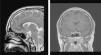

En la RM craneal se objetivó la presencia de un microadenoma hipofisario (3mm×5mm). Con todos estos datos se realizó el diagnóstico de enfermedad de Cushing (fig. 2).